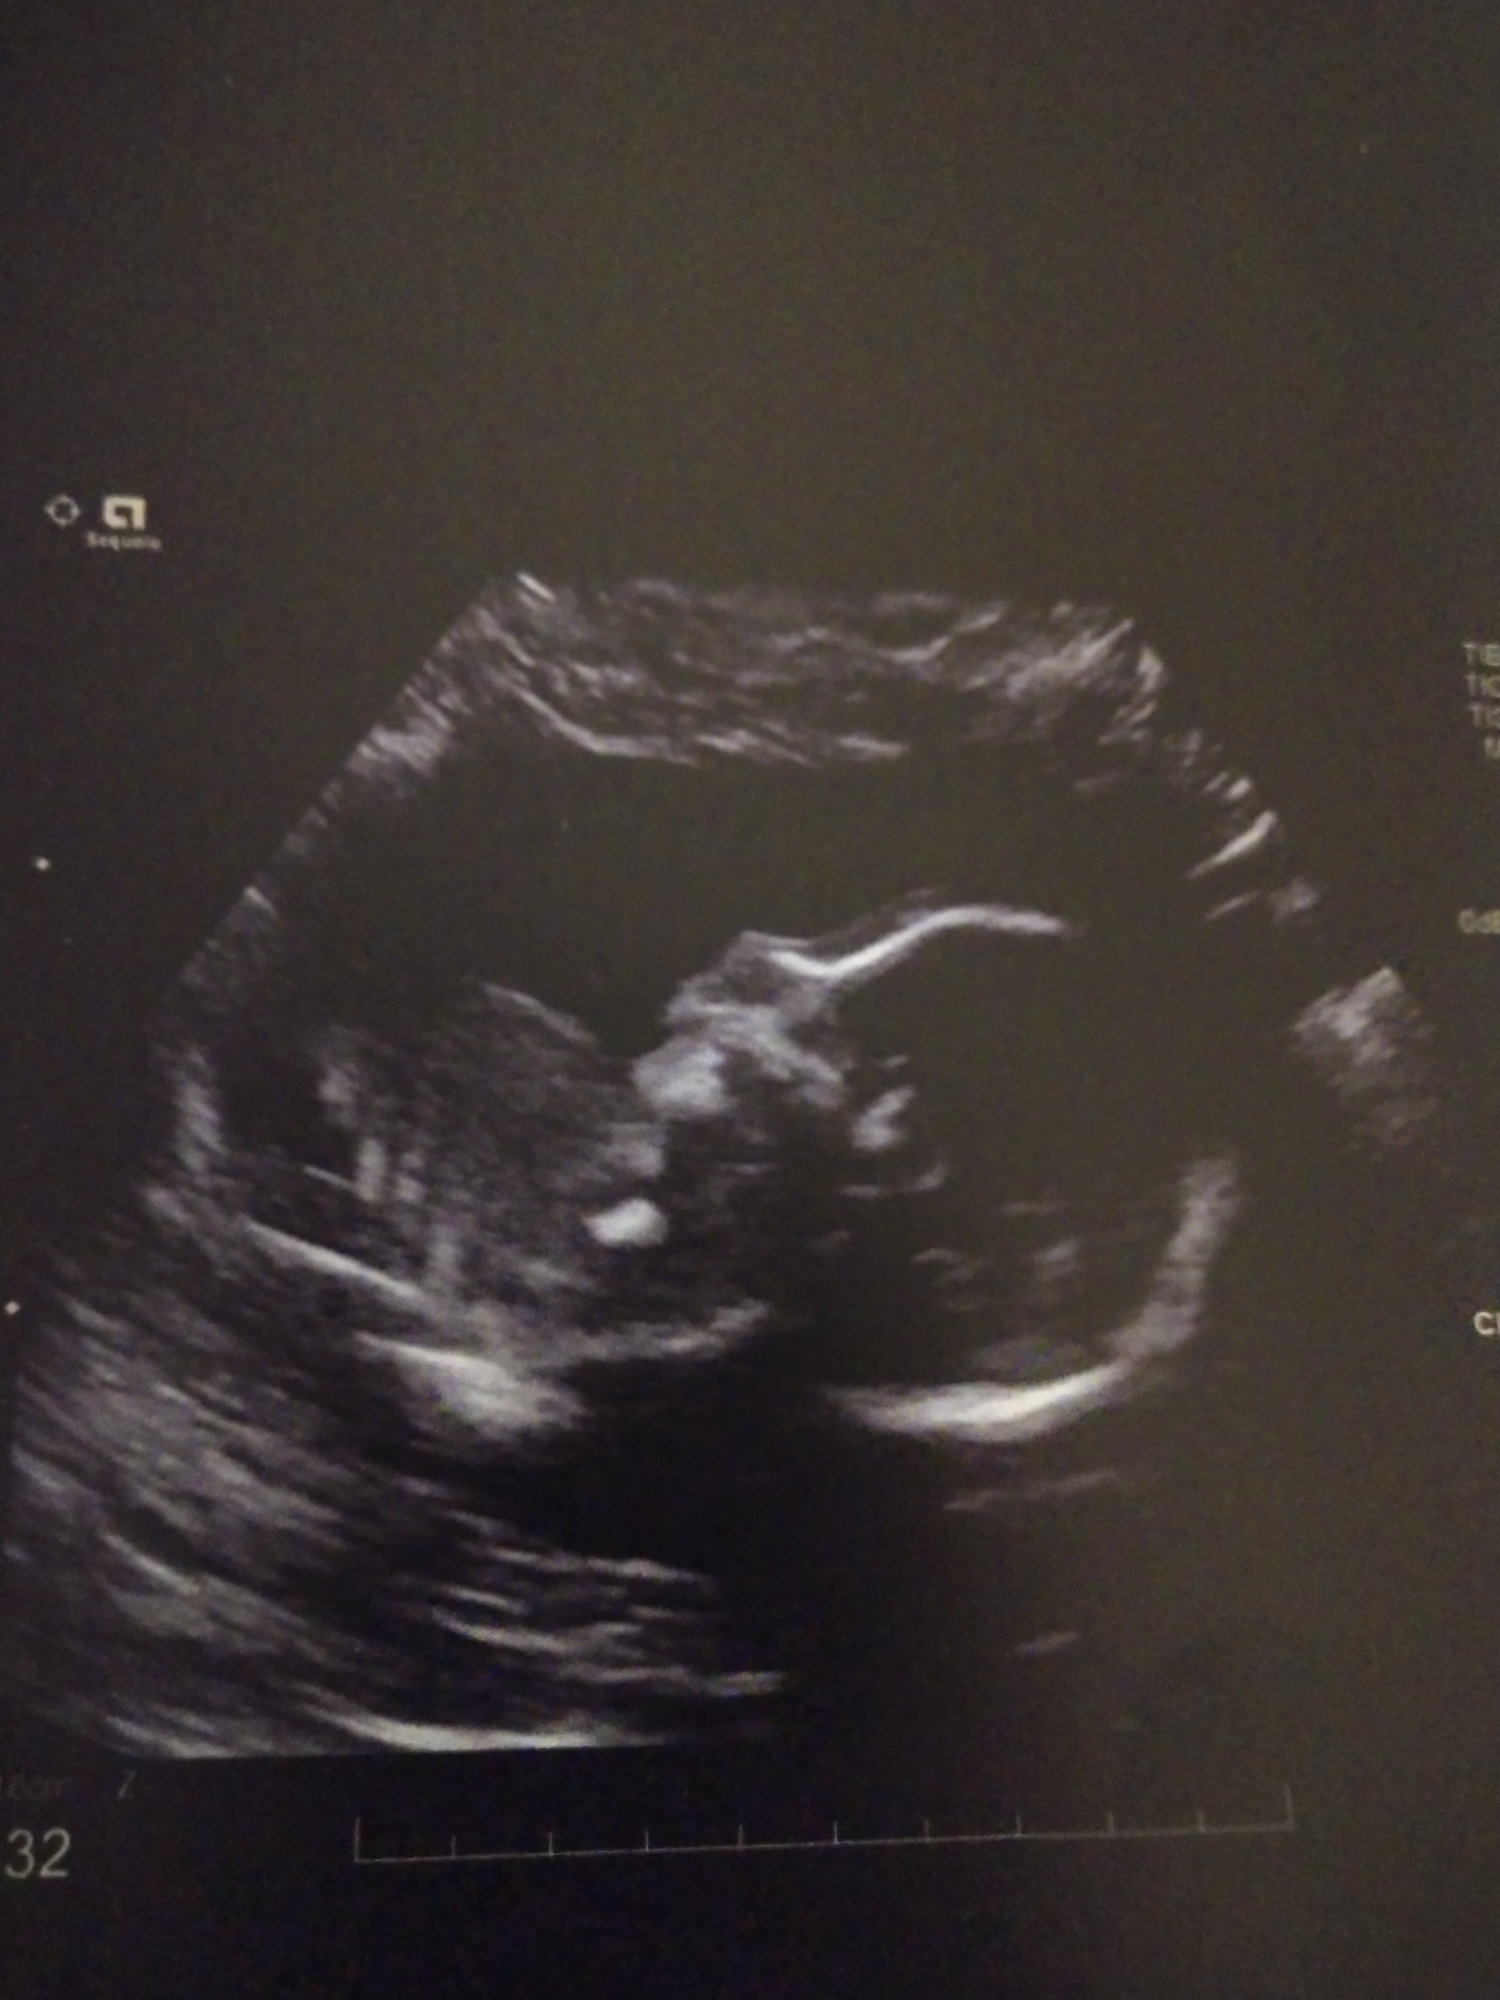

Anatomy scan today at 21W5D (they say 21W6D, but I know when I ovulated). Other than a calcium deposit found in the heart, everything looked good. Kind of stressed about it but hoping for the best.